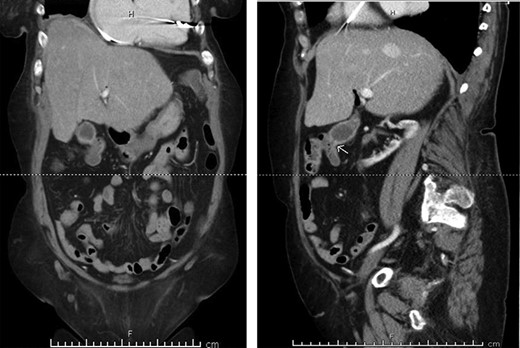

A 70-year-old female with congestive heart failure, atrial fibrillation, and end-stage renal disease presented to the general surgery clinic with a radiographic finding of a CCF. During workup for upper gastrointestinal bleeding, a computed tomography (CT) enterography incidentally demonstrated a fistulous connection between her gallbladder and the proximal transverse colon (Fig. 1). In the clinic, she reported right upper back pain that was unrelated to meals. She had no abdominal tenderness and her liver function tests were within normal limits.

Preoperative CT enterography demonstrating a CCF; (a) coronal view and (b) sagittal view, the white arrow indicates the location of the fistula.

In this study, we were able to track the evolution of the patient’s cholecystoenteric fistulae. She was managed by the same surgeon over the 5 years from her initial episode of cholangitis to her eventual cholecystectomy. The initial CT scan taken during her hospitalization shows an inflamed gallbladder abutting the proximal transverse colon (Fig. 2). The CT enterography obtained 5 years later depicts a fistula that developed in this same region (coronal and sagittal views, Fig. 1). Intraoperatively, the fistula was also found at this location. It is difficult to ascertain when the fistula developed as the patient may have been asymptomatic for years.